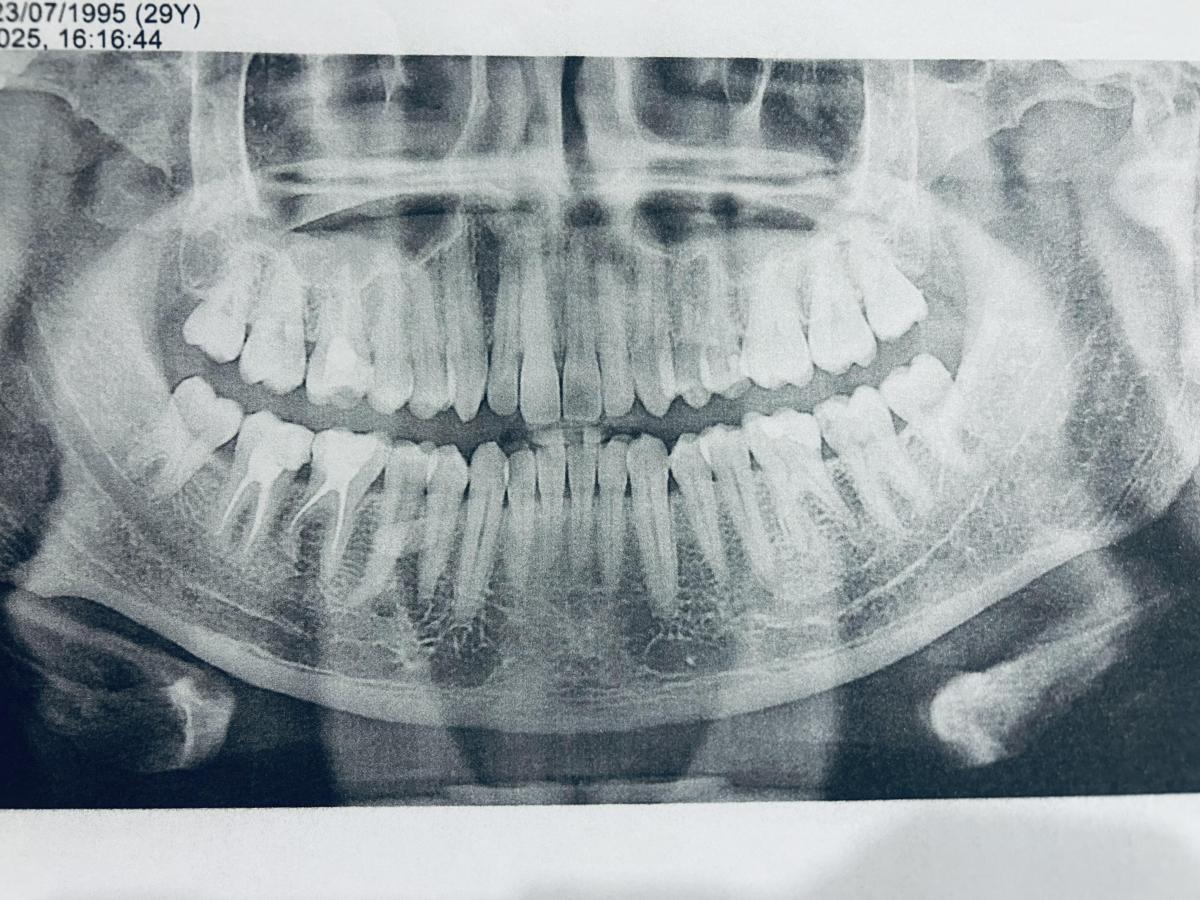

1. Действительно ли удалось спасти зуб, какой по нему прогноз? (Сейчас не беспокоит, первый рентген – август, второй – свежий, но на нем смущает, что темнота прямо у стенки канала, заметил только дома).

Воть! Панорамный снимок буквально за 1,5 месяц до реагирования 36 на горячее. Ничего про него не сказали. Сосед - 37 если что пролечен сразу после снимка

iren28, спасибо! Вот свежий снимочек, внизу темноты будто стало побольше, что думаете?

Юрий Жигурт, прикольно… но вот видна динамика за этот год, она положительная или все плохо

Mayerkirill, в предыдущем ответе я не высказал то, о чём думаю, а констатировал факт! Мысли высказывать не буду, потому что народ обижается на мои мысли... А, вот если Вы хотите получить более-менее достоверную информацию о динамике, то надо делать снимки, которые позволяют, эту самую динамику, проследить! Проведённое обследование предоставляемое Вами, не является достоверным для определения динамики, для этого надо делать КТ (причём желательно на одном и том же аппарате). В предоставленных обследованиях динамику определяют с большой натяжкой, т.к. проведение обследования на другом аппарате и изменение позиционирования головы на том же аппарате до 1 градуса, может изменять размеры объектов на 20 процентов и более... Это констатация факта!